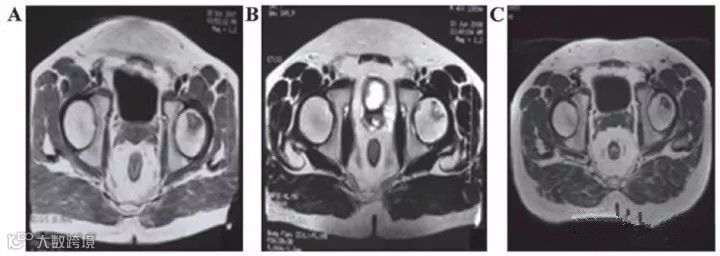

表8 :刘颖、谷涌泉应用脐带MSC治疗股骨头坏死的临床研究结果

吉林省组织工程重点实验室刘颖教授、首都医科大学宣武医院谷涌泉主任等,对9位骨循环协会评级为II-IIIa级的股骨头坏死患者经大腿动脉输注脐带间充质干细胞后,患者的红细胞、血小板、血氧转运指数明显改善。MRI检测显示24个月后股骨头坏死区域体积显著减少。